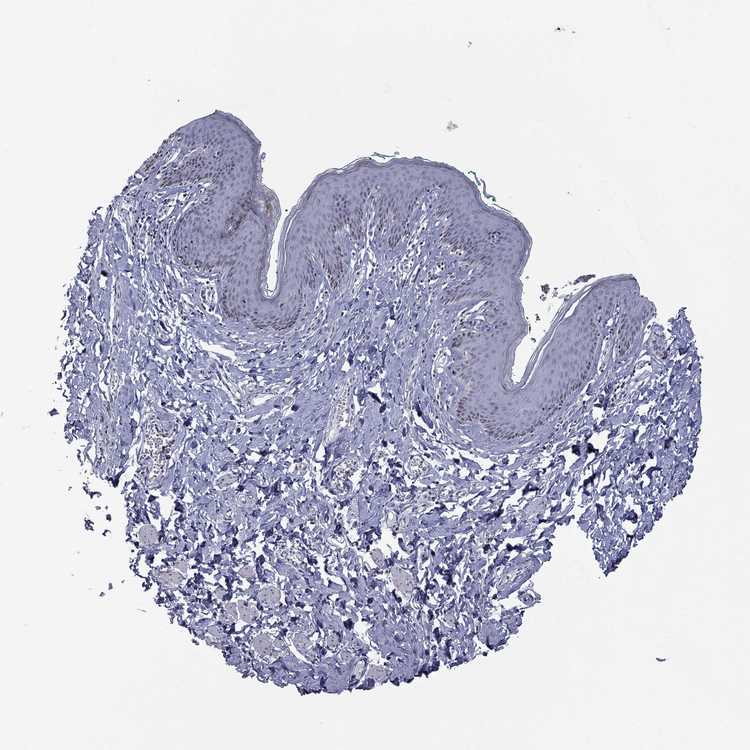

SKIN 1 - Antibody stainingi

Antibody staining in the annotated cell types in the current human tissue is reported as not detected, low, medium, or high, based on conventional immunohistochemistry profiling in selected tissues. This score is based on the combination of the staining intensity and fraction of stained cells.

Each image is clickable and will lead to virtual microscopy that enables deeper exploration of all samples and also displays staining intensity scores, fraction scores and subcellular localization as well as patient and tissue information for each sample.

Antibody HPA076284

Langerhans Medium

Fibroblasts Not detected

Keratinocytes Not detected

Melanocytes Not detected

SKIN 2 - Antibody stainingi

Epidermal cells Low